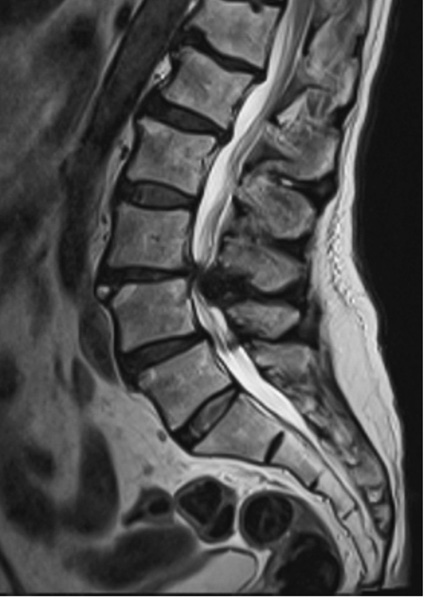

Lumbar Laminectomy

Laminectomy is a surgical procedure involving removing part of the vertebral bone called the lamina.

The lamina is a flat, thin vertebral arch component covering the spinal cord and nerves.

Generally, laminectomy is carried out to ease the pressure on the spinal cord or spinal nerves that results from conditions like spinal stenosis, spinal tumours, or herniated discs.

The narrowing of the spinal canal can compress the spinal cord and nerves, leading to various symptoms, including pain, numbness in the lower back, hips, legs, and feet and, rarely, weakness. The severity of these symptoms depends on the extent of the stenosis.